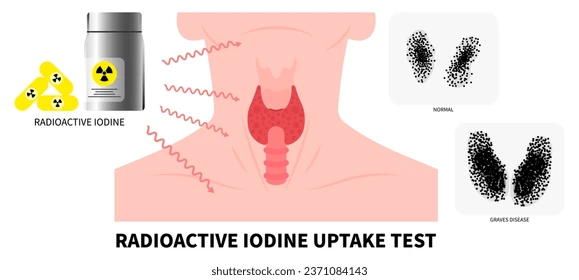

Radionuclide therapy offers a range of treatments for challenging medical conditions, with some being the preferred option for specific ailments. Among these, radioiodine therapy stands out, particularly for addressing hyperthyroidism and thyroid cancer.

- Radioactive Iodine I-131, a beta-emitting isotope derived from stable iodine, naturally resides in the thyroid gland. This gland, located in the neck, regulates metabolism by producing hormones. When the thyroid becomes overactive, it generates excessive hormones, leading to conditions like hyperthyroidism, often caused by Graves’ disease or nodules within the gland.

- Administering a small dose of I-131 orally allows it to be absorbed into the bloodstream through the gastrointestinal tract. The thyroid gland then concentrates the radioiodine, initiating the destruction of its cells. Any surplus radioiodine is primarily eliminated through urine, swiftly exiting the body. This therapy is highly effective for managing hyperthyroidism and is often the preferred treatment.